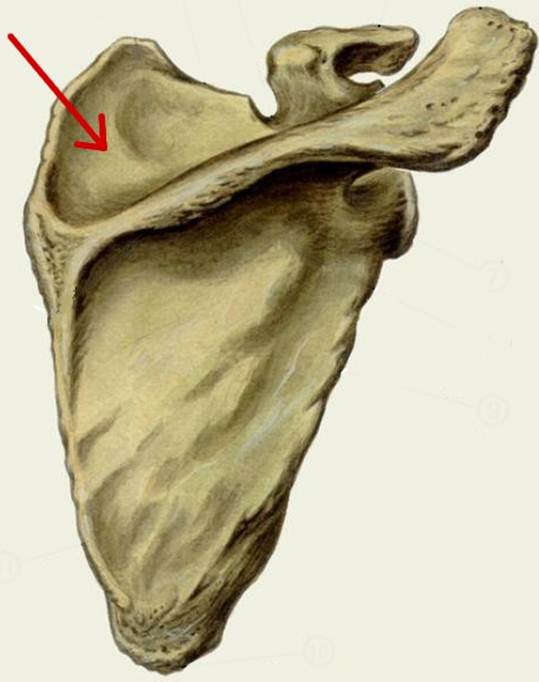

I:

S: Стрелка указывает на incisura scapulae (латинский язык).

S: Стрелка указывает на fossa supraspinata

S: Стрелка указывает на angulus superior